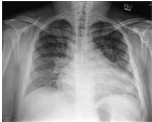

患者入院后胸部X线检查(图1)显示心脏肥大,心脏胸廓比为0.62,肺纹理增粗明显。心电图检查提示,有不完全性右束支传导阻滞,右心房与左心房肥大。

图1 胸部X光显示,心脏肥大及两侧肺血管充血。